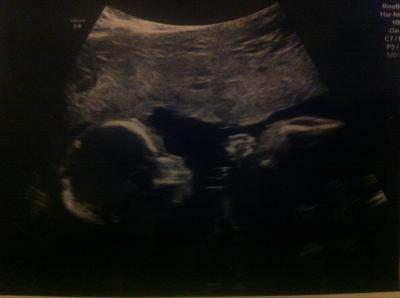

Huhu Mädels, war ja heut bei der FD.. alles wunderbärchen. Ist und bleibt ein junge ;) ist 436gr schwer und ca 25cm groß.. Haben recht lang geschallt und darf/soll in 5-6 Wochen nochmal hin (der Herr hat sich immer so weggedreht dass manche Sachen schwer zu schallen waren ;) ) Hab auch ein Super Bild mitbekommen.. So n komplett Bild mit Bein, Hand und Gesicht :)) Wünsche euch allen eine gute Nacht, ich hau mich jetzt hin :*

Bild zu FD Ergebnis :) - Forum für April - Mamis